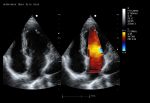

El Doppler Color ViV 20 es un ecógrafo de nueva generación diseñado para ofrecer una experiencia clínica superior con un equilibrio perfecto entre rendimiento, durabilidad y accesibilidad. Su arquitectura avanzada proporciona imágenes claras y precisas, permitiendo diagnósticos confiables en aplicaciones como abdomen, ginecología, vascular, partes blandas y más.

Práctico y fácil de usar, el ViV 20 integra funciones esenciales para el trabajo diario, con herramientas de medición completas, modos Doppler avanzados y optimización automática de imagen. Su diseño resistente garantiza una larga vida útil incluso en entornos de alta demanda, convirtiéndolo en una opción ideal tanto para clínicas pequeñas como para centros médicos con gran flujo de pacientes.

Imágenes clínicas extraordinarias

| Aplicaciones | Cardiología, abdomen, vasos sanguíneos, estudios generales |